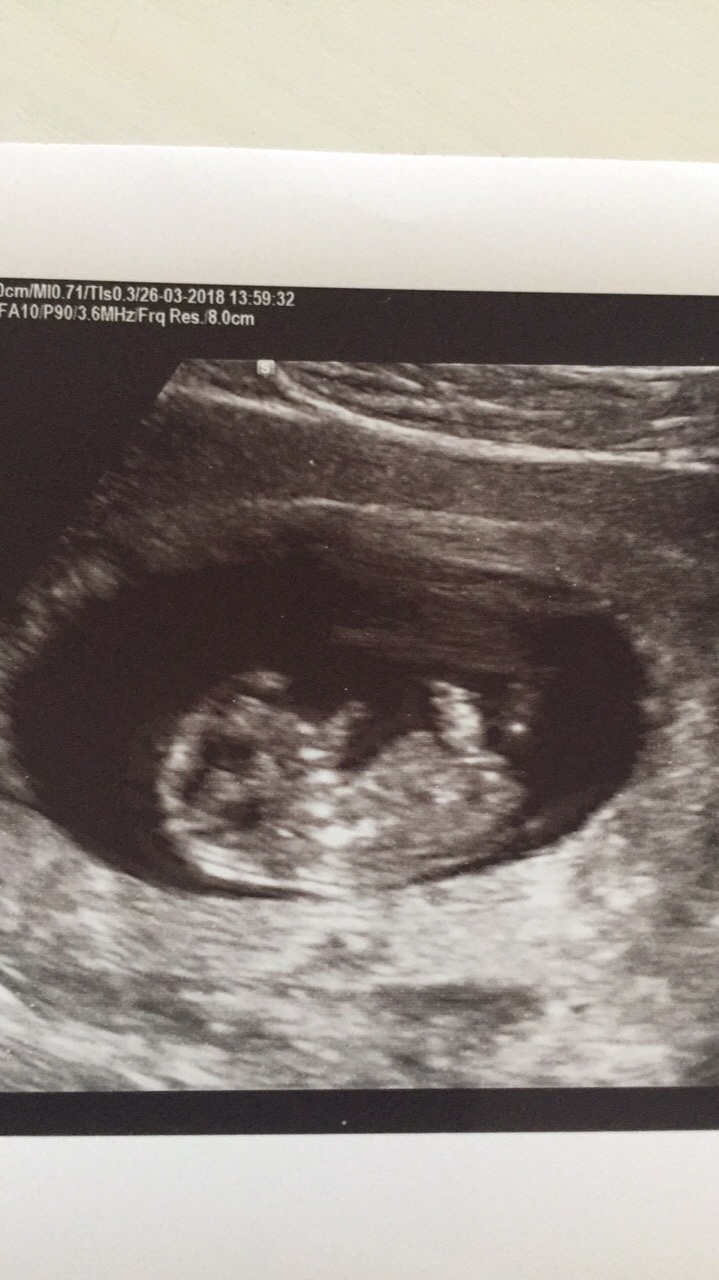

Akkurat ferdig med TUL, vi fikk se og høre ett bankende hjerteHelt i lykkerus

Jeg er 8+2 i dag.

Jeg har vært på en privat ul idag, 7+3, og fikk se den lille og fikk høre et bankende hjerte. Fantastisk lyd!

Gyn kunne se at den andre fostersekken ikke hadde utviklet seg videre, så nå er vi helt sikre på at vi venter én baby og ikke to. Godt å få vite det helt sikkert med tanke på planlegging, og jeg er uansett kjempefornøyd med en.![]()

Bamsemumsen vår har blitt et lite miniatyrmenneske, og alt ser tipp topp ut[emoji173]️[emoji173]️

Så gøy at den lille ser ut som et lite menneske allerede! Mener å huske at du er akkurat to uker lengre enn meg, 9+3, stemmer det? Hvor stor er den lille da? Legg gjerne ut bildet, da, så vi får se det lille miniatarmennesket deres.![]()